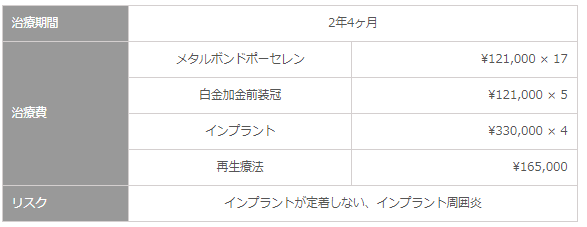

治療期間・治療費・リスク

治療後のリコール時におけるリスクマネジメント

- 3ヶ月に1回のリコールにて、全顎的な咬合の調整と、歯周疾患の管理。

- インプラント歯周炎に対しては、炎症の除去を徹底的に行い、骨へのダメージがいく前に対応致します。リコールによる、維持治療を行います。